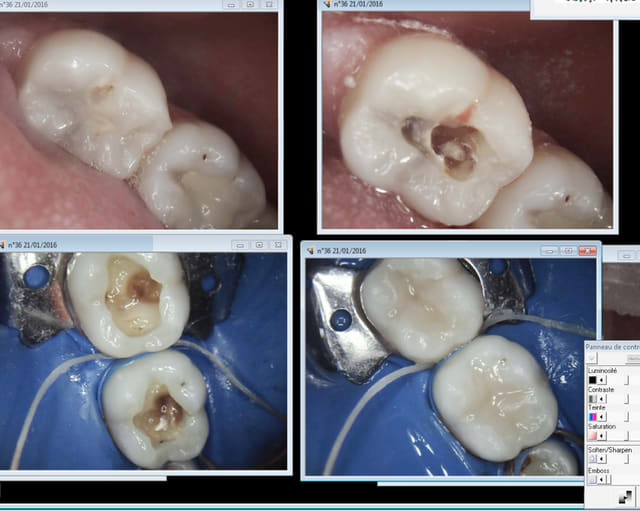

C'est sur on les martyrise les patients, on leur colle des truc pas possible en bouche et en plus on les arnaque. 19,28 euros le composite une face, sous digue.

Ici reprise de carie sous composite à 99,9 % pas fait sous digue.

> Ici reprise de carie sous composite à 99,9 % pas fait sous digue.